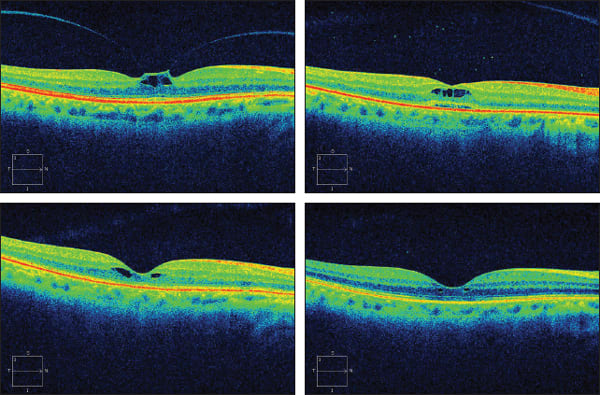

The goal of vitrectomy for many vitreoretinal disorders is to cleave the posterior hyaloid from the retinal surface. Obtaining a successful surgical outcome generally depends on how effectively and completely this is achieved. For more than two decades, investigators have searched for a pharmacologic agent to create the same vitreoretinal separation nonsurgically for the treatment of tractionally based disorders, such as symptomatic vitreomacular adhesions (VMAs; Figure 1) and macular hole, as well as diabetic macular edema, cystoid macular edema (of multiple etiologies), retinal detachment, proliferative vitreoretinopathy, trauma, retinopathy of prematurity (ROP), and other pediatric retinal diseases.

Figure 1. Classification scheme of hyaloid adhesion and vitreomacular traction (VMT) seen with SD-OCT. A normal eye of an elderly patient: The hyaloid membrane is visible and completely detached from the fovea, though there is a persistent adhesion to the optic nerve (top). Eye with nonexudative AMD and drusen (center): The hyaloid is attached over the entire macula, including the fovea. Eye with choroidal neovascularization (bottom). The persistence of hyaloid adhesion causes VMT over the CNV complex: A focal distortion of the retinal profile is visible at the site of hyaloid attachment. Reprinted from Am J Ophthlamol, vol. 146, Mojana F, Cheng L, Bartsch DU, et al., The role of abnormal vitreomacular adhesion in age-related macular degeneration: spectral optical coherence tomography and surgical results, pp. 218-227, Copyright 2008, with permission from Elsevier.